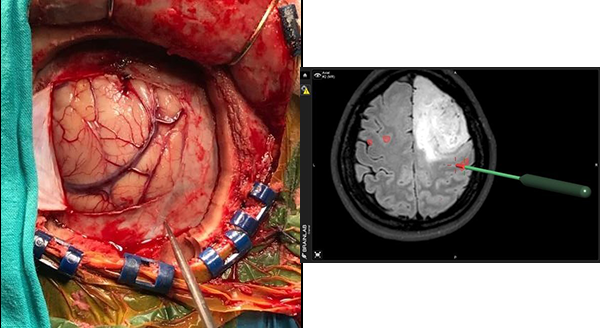

La cirugía se inicia, realizando en la estación de trabajo del navegador Brain Lab Vector Vision II la fusión de imágenes pre quirúrgicas establecidas en el protocolo de neuronavegación antes mencionado por un procedimiento de fusión automática. La secuencia funcional BOLD se fusiona de manera manual, ajustando el tiempo que duran las tareas motoras y los períodos de descanso.

Una vez anestesiado el paciente y fijo a un clamp de Mayfield se realiza el co registro de las imágenes pre quirúrgicas con el paciente a través de registros indirectos de fusión de superficie (Surface Matched) por registro infrarojo, ó por registro directo de imágenes con tomografía computada intraoperatoria (RDII). Esta forma de registro directo elimina los errores de registro indirecto por sistema infrarrojo o electromagnético. Pero su máxima utilidad es permitir la fusión de las imágenes cualquiera fuese la posición quirúrgica de la cabeza ya que la TC intraoperatoria hace visible todo el volumen del cráneo para su correcta fusión con el resto de las imágenes pre quirúrgicas.

Con ayuda de la herramienta de corte se planifica una craneotomía ajustada al criterio de abordaje mínimamente invasivo que exponga los límites del tumor y el área funcional motora indicada por la RMf.

- Monitoreo Neurofisiológico Intraoperatprio

Realizado el colgajo dural el primer paso es la identificación del surco central por sus características morfológicas en la secuencia T1 de la RMN. Luego se procede a corroborar la funcionalidad cortical pre y post central de la corteza anatómica observada en la RMN, con ayuda de un electrodo de cuatro polos para verificar la inversión de fase de la onda de respuesta N20 en un registro de Potencial Evocado Somato-Sensitivo por estimulación eléctrica del nervio mediano contralateral a la lesión, esto permite la localización neurofisiológica del surco central.

3º Colocación de etiquetas numeradas sobre la superficie cortical, y estimulación espacial cortical directa (ECD)

El tercer paso del monitoreo intraoperatorio es la colocación de stickers numerados que nos permitan reconocer la relación espacial de la corteza quirúrgica con al área de activación de la RMfm. De esta manera se colocaron sobre la superficie cortical distribuyendo en forma aleatoria etiquetas estériles numeradas de 0.5 x 0.5 cm. separadas por una distancia aproximada de 1 cm. Las etiquetas cubrieron toda el área de la craneotomía incluyendo la corteza del tejido funcional registrado en la RMfm (expuesto en el abordaje) y la superficie cortical del tumor. Luego se procedió a la estimulación cortical directa (ECD) con estimulación bipolar con una corriente inicial de 4 mAmp, y si no se obtenían respuestas se incrementó sucesivamente a 8 y 12 mAmp. una frecuencia de 60 Hz y tres pulsos de 0.2 mseg de duración.

La respuesta motora fue evaluada por el neurofisiologo del equipo quirúrgico.